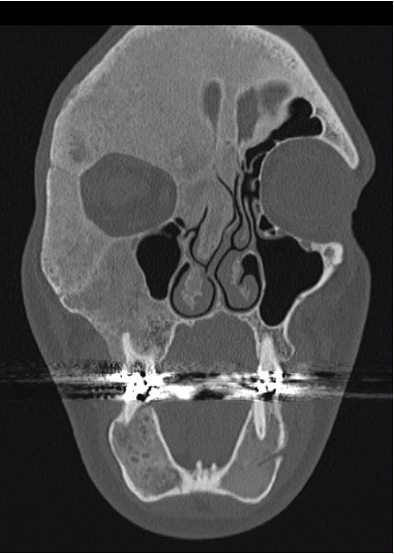

1. Je me posais la question de l’efficacité d’un traitement anti-ostéoporotique (les bisphosphates) dans la dysplasie fibreuse, une maladie rare qui fragilise les os des membres et du visage. En particulier je souhaitais évaluer l’effet de ces traitements sur la réduction de la douleur des patients puisque les études prises isolément étaient peu contributives.